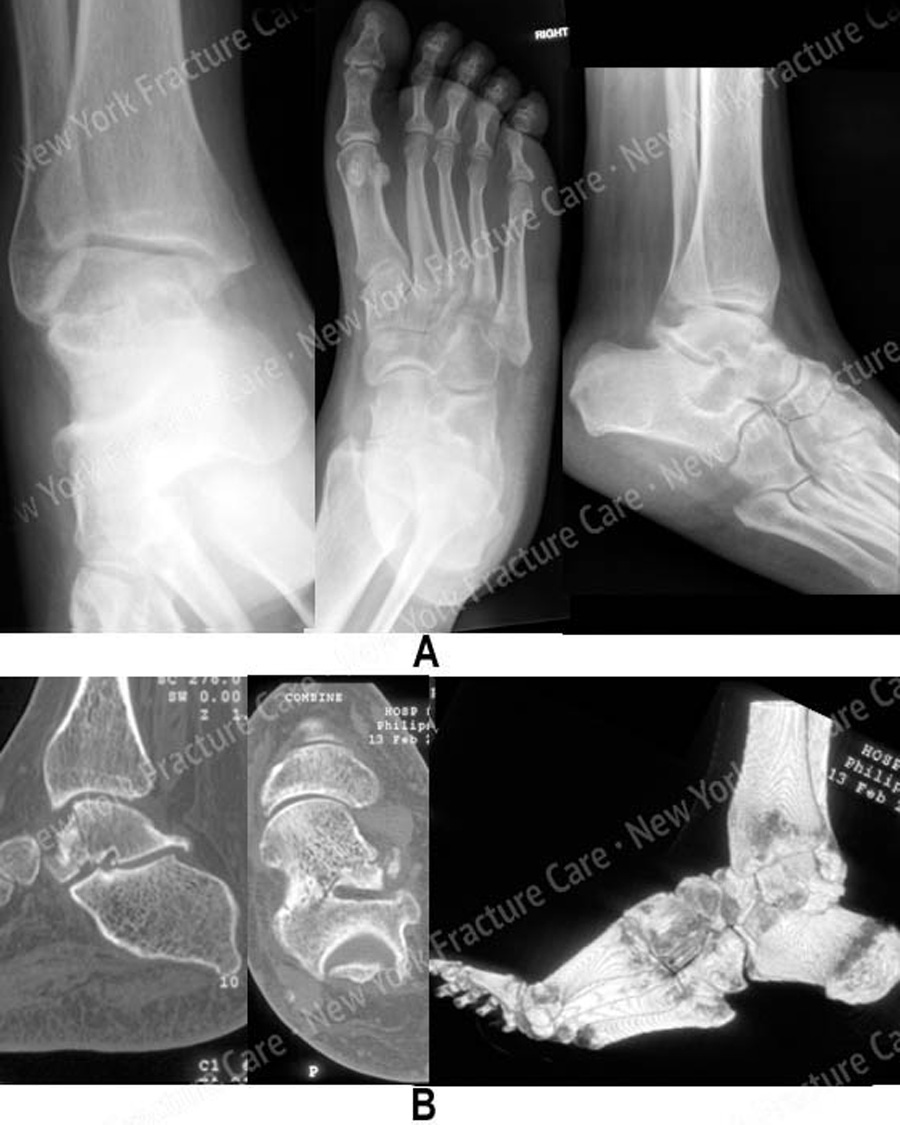

From nyfracture.com

Talus fractures (foot) New York Fracture Care Fracture Talus Treatment Treatment plan • place in temporary splint once talar neck fracture reduced • time to definitive fixation not related to increased risk of avn •. A joint called the mediotarsal separates your hindfoot from your midfoot. The lisfranc joint separates your midfoot from your forefoot. Find out how to tell if your ankle is broken (fractured) and when to get. Fracture Talus Treatment.